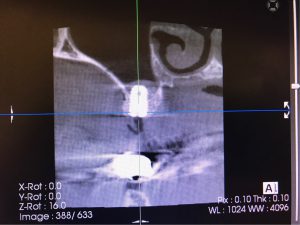

今日は朝一からインプラントオペ

本日は他院からのご紹介をいただいた患者さまの

インプラントオペをセデーション下でさせて

いただきました!

早ければ2ヶ月で歯が入ります

うえはら歯科医院のインプラント↓